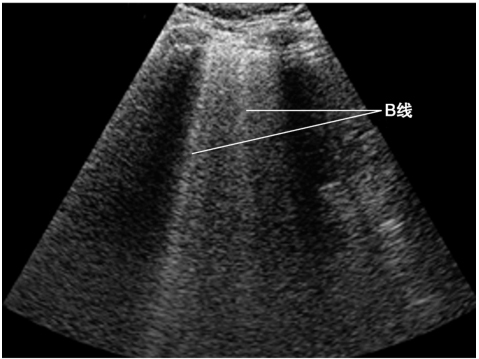

(2)B征象

B线是起自胸膜线与之垂直地随肺滑动而运动的高回声亮线,伴有“彗星尾”征,反映了其周边肺组织内的特殊的“液-气混合状态”,同一切面出现3条以上B线提示肺间质综合征的存在(图3)。因为肺炎病灶在肺内往往并不呈对称分布,因此可以表现为肺叶之间或同一肺叶内部不同区域分别存在B征象和A线(即残留有正常肺组织的区域)。需要注意的是,当有胸腔积液时,类似的高回声亮线起自肺表面,该伪像称为假B线,并不能作为反映肺实变的可靠依据(图4)。

图3 B线